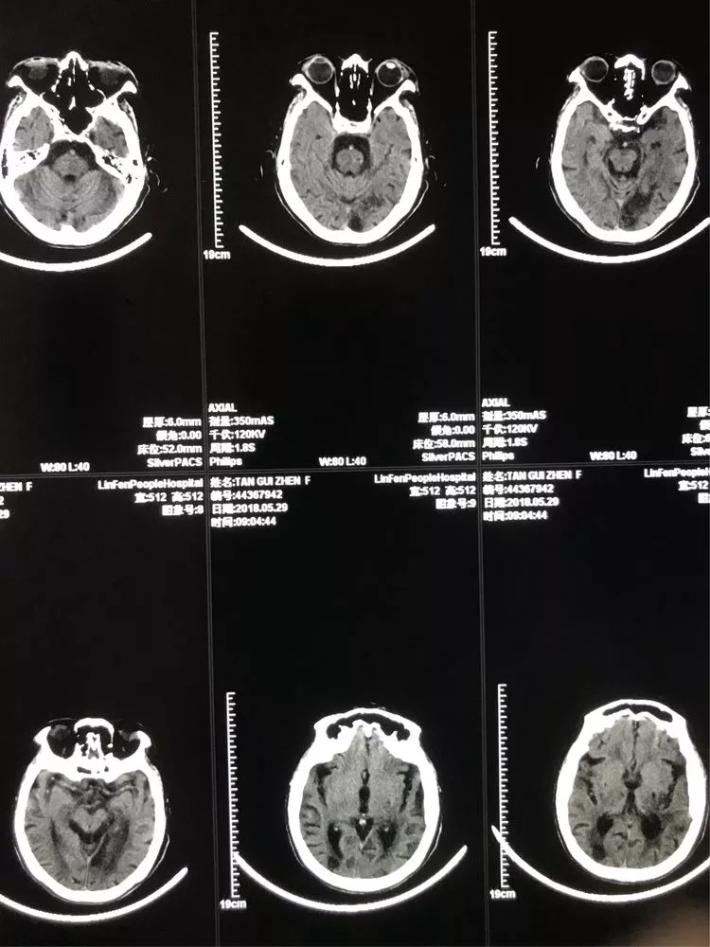

女性,61岁。主因突发左侧肢体瘫痪3小时急诊入院。颅脑CT未见出血。Nihss评分8分。急诊溶栓,同时行MRA检查。

MRA显示:左侧大脑中动脉闭塞。

患者女性,64岁。主因突发右侧肢体瘫痪3.5小时急诊入院。颅脑CT:未见出血。Nihss评分18分。急行静脉溶栓,同时MRA检查。

MRA显示:左侧颈内动脉闭塞。